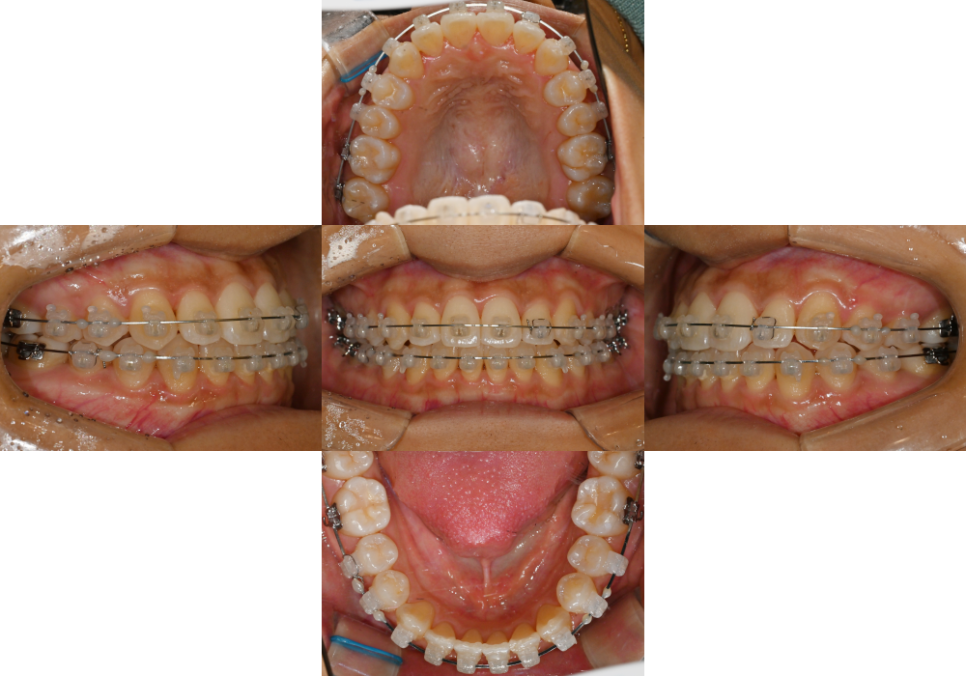

구강 내 모습을 먼저 보겠습니다.

먼저 위아래 치열이 삐뚤고,

윗니가 아랫니를 안정적으로 덮지 못하고

절단연 교합인 것을 확인할 수 있습니다.

더불어, 양쪽 어금니가

3급 부정교합이었는데요.